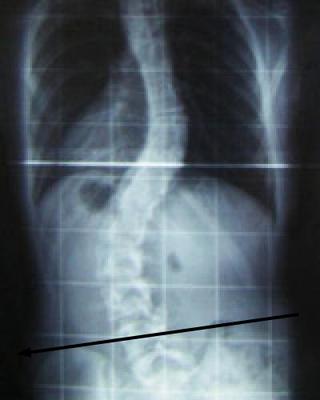

A more serious scoliosis caused by a very short leg.

It seems to me, reading between the lines that you have a mild scoliosis and, at the apex often in the lower middle back, there is often discomfort or pain.

Very often that scoliosis is caused by a short leg which frequently causes fixations in the sacroiliac joints. The treatment you describe was probably for that, and I would probably have done much the same.